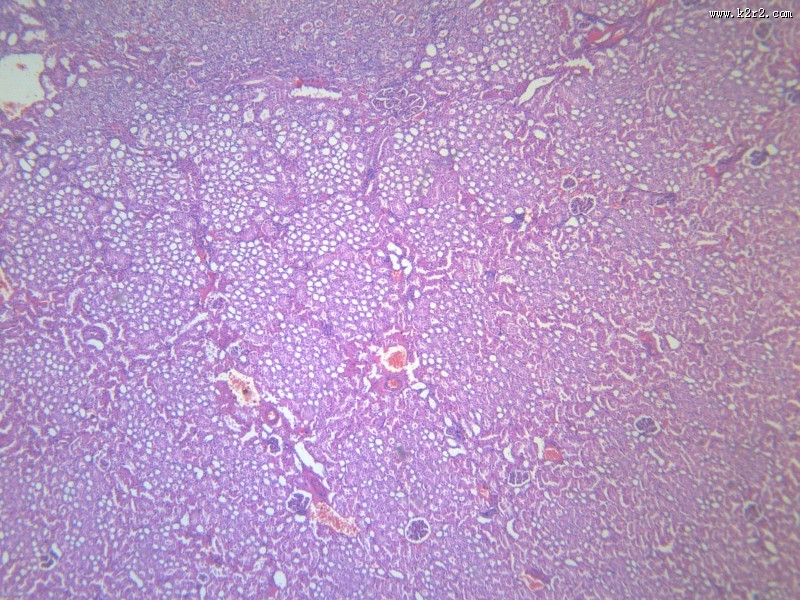

肾凝固性坏死 - 第5张

肾凝固性坏死

kidney coagulative necrosis